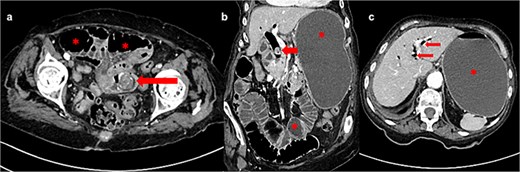

(a) Dilated bowel loops with ischemic part adjacent to the gallstone (pointed by grasper); (b) massively dilated stomach; (c) stones found in the jejunum (the larger one) and the common bile duct (the smaller one).

An 88-year-old lady was admitted to our institution due to vomiting for 4 days and hematemesis on admission. The patient was icteric, hypotensive, with a distended abdominal wall and periumbilical pain on palpation. Her past medical history included permanent atrial fibrillation on warfarin, hypothyroidism, and chronic kidney disease. Laboratory testing revealed leukocytosis (leucocytes 13.3 × 109/L), normal hematocrit (0.36 L/L), elevated C-reactive protein level (CRP 89 mg/L), INR >6.0, glomerular filtration rate of 25 ml/min/1.73 m2, elevated bilirubin level (total bilirubin 57 μmol/L; reference range 3–20) as well as elevated hepatic aminotransferases [alanine aminotransferase 76 U/L (reference range 10–36), aspartate aminotransferase 113 U/L (reference range 8–30), gamma glutamyl transferase 54 U/L (reference range 9–35), alkaline phosphatase 87 U/L (reference range 64–153)]. Abdominal computed tomography (CT) scan showed intestinal obstruction in the jejunum caused by a gallstone, a gallstone in the dilated bile duct, stomach/jejunal dilatation and hepatic pneumobilia (Fig. 1). The patient received prothrombin complex concentrate, vitamin K, and other resuscitative measures before undergoing emergency surgery via median laparotomy. Intraoperatively, the small intestine was distended orally from the incarcerated 3 × 3 cm gallstone at 50 cm from the Treitz ligament and with subsequent tiger-stripe ischemic changes of the jejunum proximal to stone impaction (Fig. 2). Additionally, a cholecystoduodenal fistula and a 15-mm gallstone in the common bile duct (CBD) were found. The cholecystectomy and duodenal defect repair were performed. The gallstone was extracted from the CBD via choledochotomy and T-drainage. The ischemic part of the small intestine was resected, the gallstone was removed, and intestinal continuity was restored. Histopathology confirmed hemorrhagic necrosis of the resected intestine. After successful treatment, the patient was discharged home. One year after the surgery, the patient remained in good general health.